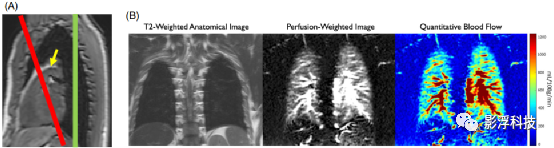

相比于肺灌注常用的CT方法,ASL的优势在于无电离辐射、无需造影剂。肺部ASL可以评估肺生理学和表征各种病理,如囊性纤维化,常用于慢性阻塞性肺疾病(COPD)和肺栓塞(PE)等疾病中。具体应用如图4所示。

图4 (A)PCASL标记平面(红色)位于肺动脉主干上方,冠状位成像定位(浅绿色)用于肺灌注成像。FAIR标记平面和成像平面位于浅绿色处。(B)健康志愿者3 T下FAIR-SSFSE序列结果。

(1)大多数肺部ASL应用均在1.5 T下进行,使用SSFSE采集和FAIR标记,如图4所示。由于心脏周期会影响成像,一般还会施加心脏门控。

(1)FAIR和PCASL两种标记方式均可用于肺部ASL,其中PCASL必须仔细规划标记平面的位置,如图4所示。